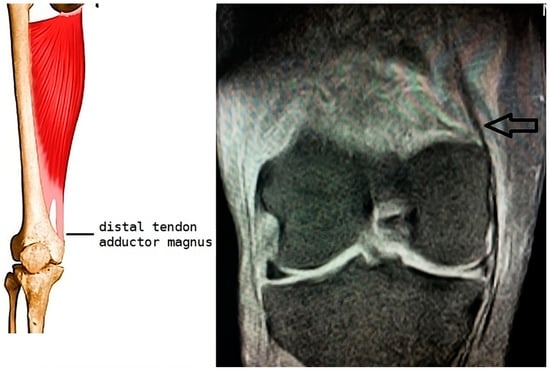

2.3. Technique Description

After receiving a thorough explanation of the procedure, the patient provided written informed consent and authorization for the anonymous publication of their case. The procedure was performed with the patient positioned on their right side. Under continuous ultrasound guidance, the calcification near the medial femoral condyle was identified, and the skin was marked to establish the needle insertion point (Figure 4). Ultrasonography assessments were also used to evaluate potential knee conditions such as osteoarthritis (KOA), effusion, synovitis, bursitis, and Baker’s cyst. These evaluations confirmed no signs of effusion, synovitis, or associated bursitis.

Equipment preparation included a 5-mL syringe with 2% mepivacaine for local anesthesia, several 10-mL syringes filled with physiological saline for lavage, and a 5-mL syringe containing 1 mL of triamcinolone (40 mg). After administering local anesthesia at the puncture site, an 18G needle was inserted under ultrasound guidance.

With continuous ultrasound visualization, pressure impulses were applied to the syringe plunger and then released to facilitate breakdown of the calcification. These pulses were repeated until the calcified material fragmented, visible as particulate matter in the syringe. Once the syringe was full, it was replaced with another containing saline solution, while keeping the needle in place. The lavage process was repeated until no further calcified material could be withdrawn. The fragmented calcified material was collected in three syringes for histological analysis, which confirmed the presence of hydroxyapatite crystals.

To complete the procedure, 1 mL of triamcinolone was injected through the needle before its removal. The entry point was covered with sterile gauze. The patient tolerated the procedure well, with no adverse reactions noted during or after the intervention. Post-procedure recommendations included resuming normal activities while avoiding prolonged standing during the week following treatment.

Figure 4. (A) Photograph showing patient and ultrasound transducer positioning for sonographically guided percutaneous lavage of the calcified tendinopathy, “X” denotes the needle skin entry site. (B) Long-axis sonogram showing the needle located over the calcification (black and white arrow). (C) Syringe with calcium material obtained in the lavage.